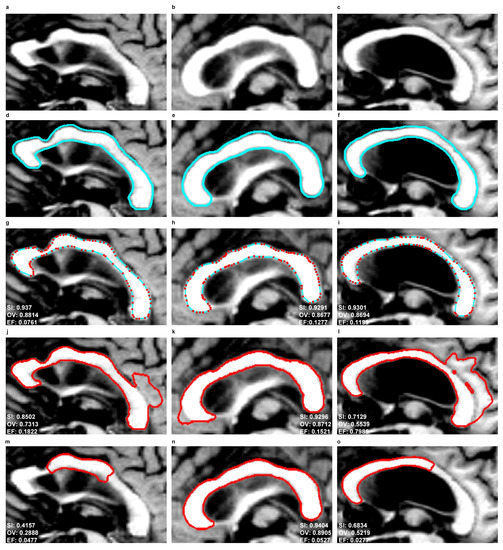

Figure 10 and Figure 11 show the segmentation results produced by the EM, SBGFRLS and DRLSE models as well as the contours manually traced by an experienced physician ( E 1 ). In the EM model, the CC contours obtained in the previous or subsequent slices of MR images can be used for initiations in the next or previous slices.

As a result of the experiments carried out, the EM model produced significantly better results of the mean SI (92%) and OV (85%) indices than SBGFRLS (SI = 82%, OV =72%) and DRLSE (SI = 73%, OV = 67%). Segmenting the CC using the DRLSE model may produce the greatest underestimation, as proven by the lowest minimum values of the S I and O V indices, which, for the DRLSE, amount to 41% and 28%, as also shown in examples from Figure 11m,o. The DRLSE and SBGFRLS models allow high segmentation results to be obtained for single CC slices, which has also been demonstrated in source articles [13,14]. However, if the entire set of CC slices is analysed as necessary to obtain an accurate 3D CC reconstruction, wrong segmentations (under- or over-segmentations) are produced for some images.

The average mean value of the E F indice is the lowest for the DRLSE model and amounts to 9%. The EM and SBGFRLS models produced mean values of the EF indice amounting to 12% and 36% respectively, so if the SBGFRLS model is used, a very high over-segmentationmay occur.

Figure 10. Comparison of corpus callosum segmentation results for example MR images taken from three sets from the MIRIAD database. First column: ‘miriad_189_AD_M_05_MR_1’, second column: ‘miriad_190_AD_M_02_MR_1’, third column: ‘miriad_205_AD_F_05_MR_1’. First row: ROIs from MR images of the corpus callosum based on the sagittal plane, Second row: contours traced by a physician ( E 1 ), Third row: contours produced by the EM model, Fourth row: use of the SBGFRLS model, Fifth row: the DRLSE model.

Symmetry 10 00589 g010

Figure 11. Comparison of corpus callosum segmentation results for example MR images taken from three sets from the MIRIAD database. First column: ‘miriad_234_AD_M_03_MR_2’, second column: ‘miriad_244_AD_F_01_MR_2’, third column: ‘miriad_257_AD_F_05_MR_1’. First row: ROIs from MR images of the corpus callosum based on the sagittal plane, Second row: contours traced by a physician ( E 1 ), Third row: contours produced by the EM model, Fourth row: use of the SBGFRLS model, Fifth row: the DRLSE model.

Symmetry 10 00589 g011